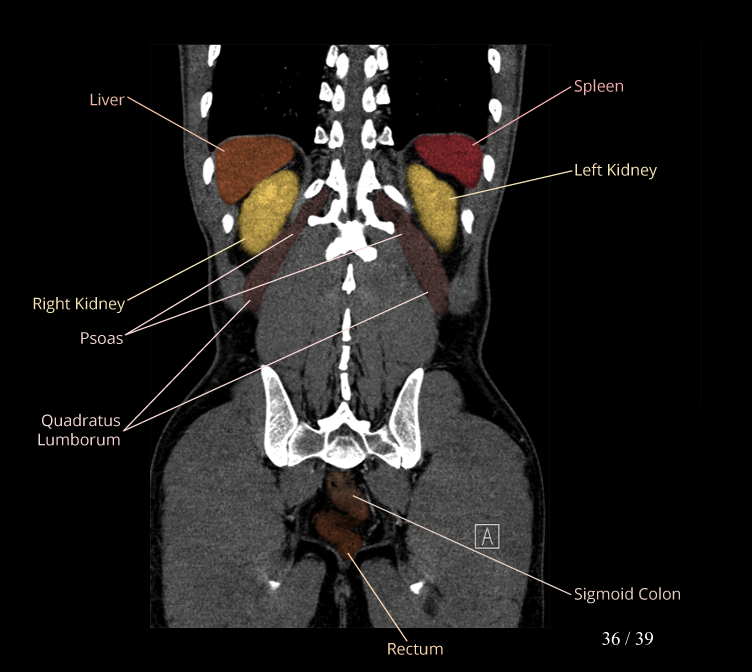

Body

Covers abdominal CT anatomy.